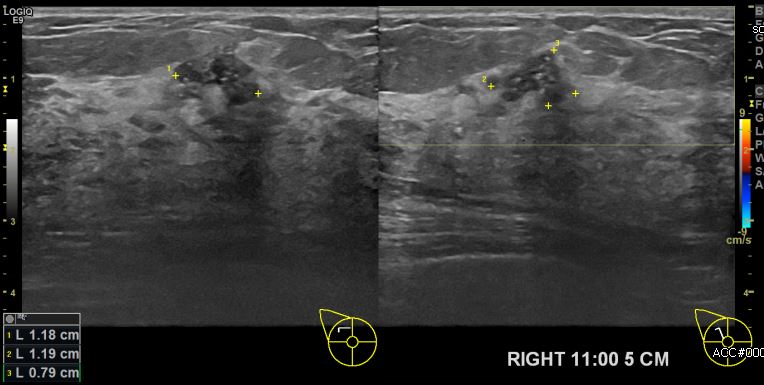

상기환자 우측유방의 멍울로 내원하신 40대 여성분으로 본원 초음파상 우측 11시 방향

5cm 떨어진 거리의 멍울 조직검사 시행하여 우측 침윤성 유관암 진단 되었습니다.